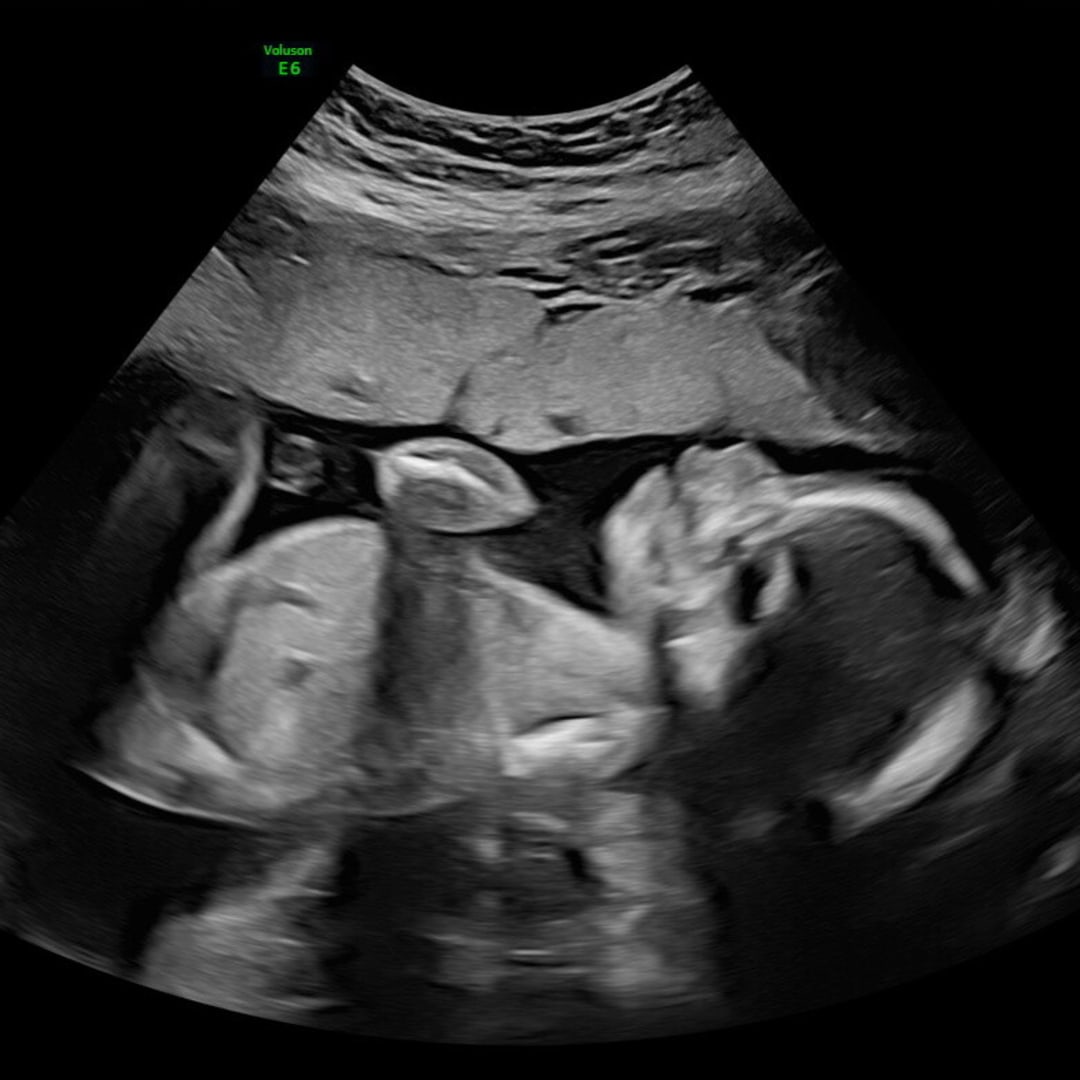

Photo shared by Abigail for their Babylist baby registry.